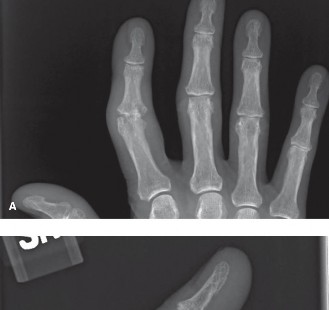

CASE 19 A 64-year-old, right-hand-dominant, Caucasian female presents to your o…

CASE 9 A 34-year-old female got into an altercation in a pub. During the cours…